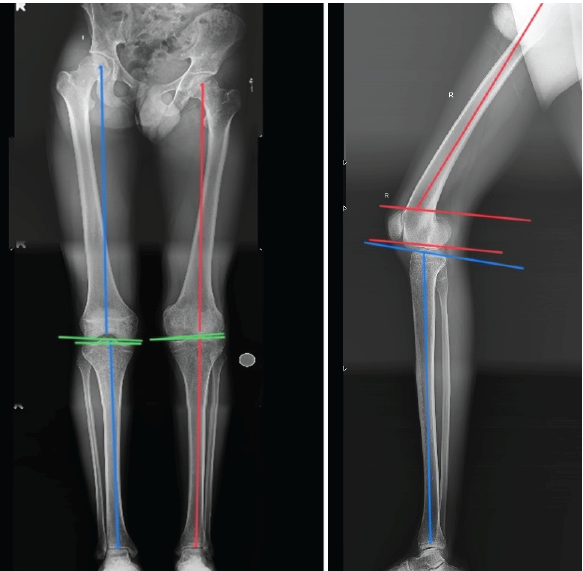

The distal femur physis was not clearly visible, suggesting that the injury was a distal femur physeal injury. Full-length radiographs of both lower limbs (Figs. 2) spanning from the hips to the ankles were taken to assess the mechanical axis of both lower limbs and to identify the pathology.

Figure 2 Skannogram of right lower limb

On assessing the radiographs, using Paley’s malalignment tests, no coronal plane deformities were seen as the mechanical medial proximal tibial angle, the mechanical lateral distal femoral angle, and joint line convergence angle were within the normal limits.

On the lateral view, the mechanical posterior distal femoral angle (mPDFA) was below the normal range of 79°, and hence our patient was diagnosed with procurvatum deformity of the right distal femur with premature closure of physis, probably due to right distal femur physeal injury, malunion, which eventually turned out to be the etiology of his FFD of the right knee. He was then planned for right distal femur supracondylar extension osteotomy (Fig. 3), where lines A, D, and E are parallel and lines B and X are perpendicular to each other. Even under the effect of anesthesia, the FFD did not reduce (Fig. 4).